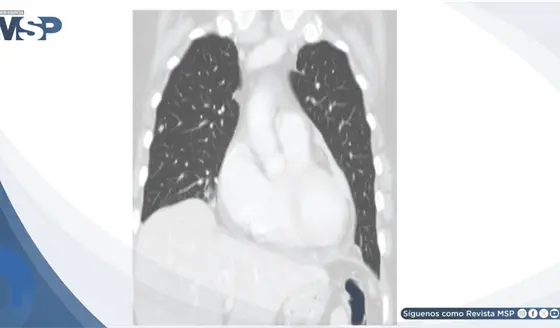

Taponamiento cardíaco como manifestación inicial de recurrencia tardía de melanoma maligno